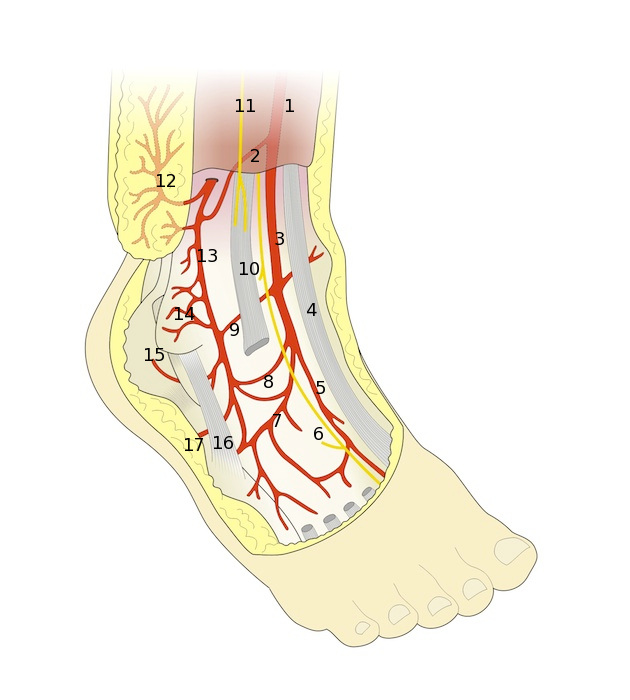

Рис. 1. Общая схема артериального кровоснабжения латеральной лодыжечной области: 1. retinaculum extensorum superius, 2. проксимальная латеральная ветвь от a. tibialis anterior 3. a. tibialis anterior, 4. m. extensor hallucis longus, 5. a. dorsalis pedis, 6. n. tibialis anterior, 7. a. tarsalis lateralis, 8. a. sinus tarsi, 9. a. malleolaris lateralis, 10. m. extensor digitorum longus, 11. n. peroneus superficialis, 12. ramus cutaneous перфорантной ветви малоберцовой артерии, 13. нисходящая ветвь перфоранта малоберцовой артерии , 14. надкостничные сосуды от нисходящей ветви перфоранта балоберцовой артерии, 15. анастомозирующая ветвь a. peroneus posterior, 16. m. peroneus brevis, 17. анастомозирующая ветвь от a. plantaris lateralis.

Перфорантная ветвь малоберцовой артерии является анатомически постоянным сосудом (Рис.1). Она всегда выходит из борозды между большеберцовой и малоберцовой костями проксимальнее дистальной большеберцовой связки, где артерия перфорирует межкостную мембрану. Перфорирующая ветвь артерии расположена на 5 см. выше латеральной лодыжки, где сразу делится на две ветви после прохождения мембраны: поверхностную кожную и глубокую нисходящую. Первая (кожная) ветвь проходит в межмышечной перегородке между длинным разгибателем пальцев и короткой малоберцовой мышцей. Далее она перфорирует фасцию и делится в подкожной жировой клетчатке, кровоснабжая кожу надлодыжечной области. Территория кровоснабжения составляет 12-18 см. в длину и 9 см. в ширину.

Вторая (глубокая нисходящая) ветвь продолжается дистально по ходу конечности, под глубокой фасцией следуя впереди латеральной лодыжки. Она анастомозирует на разных уровнях с латеральной надлодыжечной ветвью передней большеберцовой артерии. Затем артерия продолжается на стопу, где разделяется на свои терминальные ветви, формируя анастомозы с артерией пазухи предплюсны, латеральной предплюсневой артерией, малоберцовой и латеральной подошвенной артериями. В 5% случаев эту артерию заменяет хорошо развитая артериальная сеть. Анатомические вариации, связанные с уровнем анастомозов, наличием сосудистой сети вместо хорошо определяемой одиночной артерии, непостоянство наличия проксимальной ветви от передней большеберцовой артерии, не влияют на формирование кожно фасциального латерального надлодыжечного лоскута.